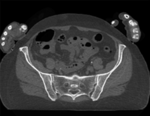

Slicer Registration Library Case 44: Visible Human Pelvis CT

This dataset contains CT of the visible human male and female pelvis. This serves as a test example for exploring non-rigid registration for inter-subject comparison from CT. The overall strategy will be to register "vhf" to "vhm" via first affine and then BSpline registration. We will generate a mask to focus the registration on the bone structure only and ignore the soft tissue when computing the deformation. Because our original images are quite large (512x512x150), we will subsample the vhf pair for use with the Deformation Field Visualizer module, which might otherwise become too memory intensive.

CT, pelvis, visible human, inter-subject